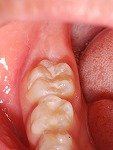

治療前に歯科器材や治療行為に慣れるためのトレーニングを行い、お子さんが泣かない、そして笑顔で治療が終えられるように心がけています。ただし外傷・歯髄炎・根尖性歯周炎など痛みを伴う緊急時は、トレーニングを行いながらの治療は難しい場合もあります。また永久歯に萌えかわる時期は、むし歯になりやすいため予防処置(フッ素塗布等)・シーラント(予防填塞)をおすすめします。

術前

→

術後